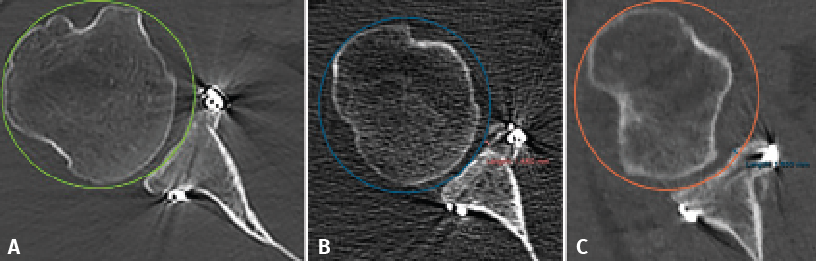

Figure 3. Evaluation of the graft position in the axial view, according to the description of Kany et al.(14). A circumference is traced over the glenoid border, and following the curvature of the latter, the amount of graft (in mm) extending beyond or failing to reach this line is measured. Image A shows the graft perfectly positioned, following the curvature of the glenoid concavity. Image B shows the graft medial with respect to the line. Image C shows the graft positioned too lateral.

The position of the graft in the mediolateral direction was evaluated in the axial sections corresponding to 50% and 25% of the glenoid height. For this purpose we used the curvature method described by Kany et al.(14); on the glenoid border and following its curvature, a circumference was traced and we quantified (in mm) the amount of defect that did not reach or surpassed that line at the point where the graft was closest to the native glenoid cavity (Figure 3). Optimum positioning of the graft was considered when the latter was located in line with the glenoid cavity, up to 3 mm lateral or up to 5 mm medial with respect to the glenoid joint border(14). Grafts protruding more than 3 mm were considered to be located lateral, while those located more than 5 mm medial to the glenoid joint surface were classified as being medial.